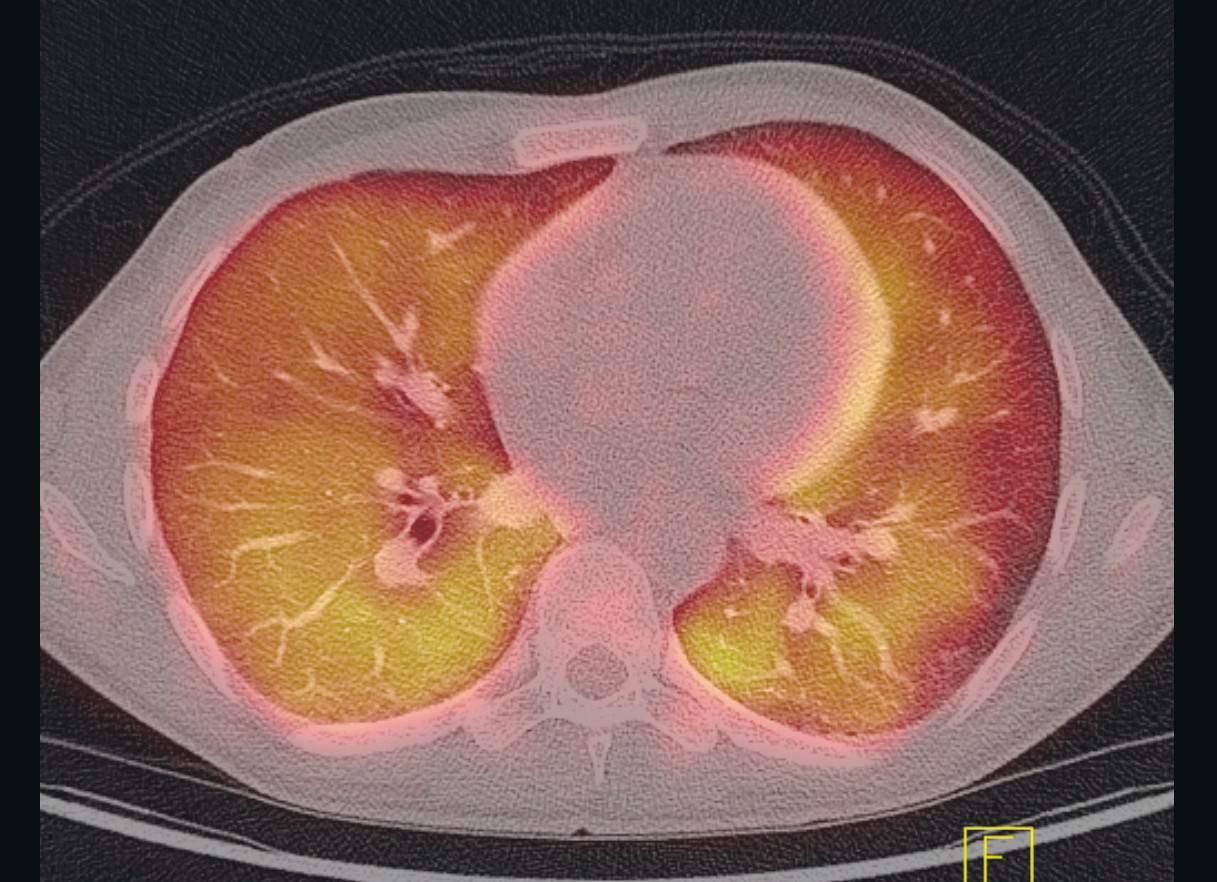

De neste dagene hadde pasienten fortsatt episoder med subfebrilia og økende dyspné, i tillegg til generelt nedsatt allmenntilstand. Det ble utført PET-CT, som viste tegn til utbredt, diffust opptak av ¹⁸F-fluordeoksyglukose (¹⁸F-FDG) i begge lunger samt reaktiv milt og beinmarg (figur 1). Differensialdiagnoser som ble foreslått, inkluderte infeksjon, lymfom og hypersensitivitetspneumonitt.

PET-CT er en modalitet der PET og multisnitt-CT kombineres. Den vanligste markøren er radioaktivt ¹⁸F-FDG, en glukoseanalog som fungerer som markør for metabolsk aktivitet i vev. PET-detektoren registrerer hvor den radioaktive strålingen konsentreres i kroppen, og dette korreleres til de anatomiske strukturene på CT-bildene. Økt ¹⁸F-FDG-opptak på PET-CT kan f.eks. ses ved økt celledeling i maligne svulster, økt aktivitet i leukocytter ved infeksjoner og ved ikke-infeksiøse inflammasjonstilstander.